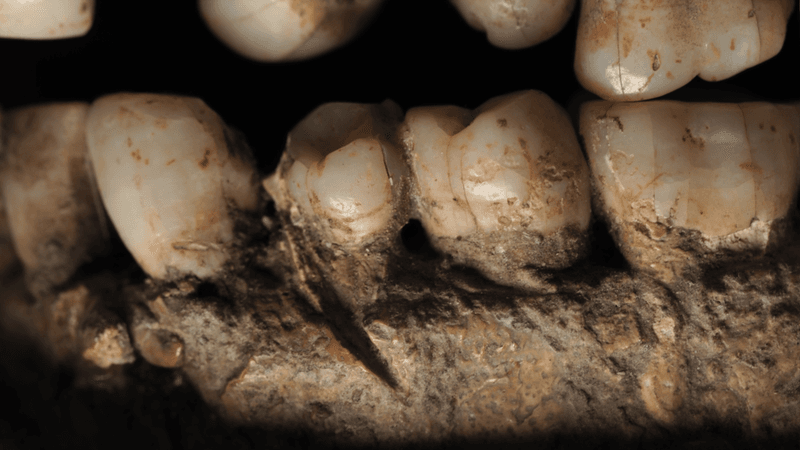

It wasn’t just the wealth of gold that showed this teen was a fortunate son. It’s notable that his teeth were in remarkably good condition with no signs of cavities, tooth loss, or disease.